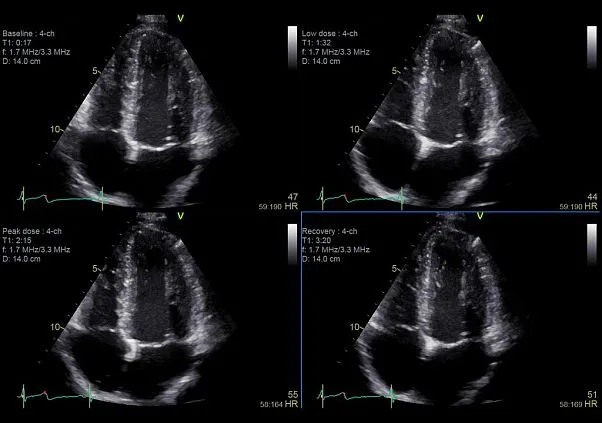

Клинические изображения

- Стресс-эхокардиография

- Smart Stress — модуль программ для проведения стресс-эхо исследований

Компактный УЗИ аппарат экспертного класса Vivid S70 с поддержкой объемной чреспищеводной эхокардиографии — 4D TEE, поднимает диагностику заболеваний сердечно-сосудистой системы на новый уровень, позволяя сделать отделения кардиоваскулярной диагностики по-настоящему передовыми и современными.

Экспертное качество изображений при проведении 2D TTE исследований и при обычной трансторакальной эхокардиографии дает возможность проводить сложные кардиологические исследования и получать достоверные результаты для назначения эффективного лечения.

- SmartStress — пакет протоколов с буфером памяти для проведения стресс-тестов с применением беговой дорожки, велоэргометра и лекарственных средств. Имеется возможность управления пользовательскими шаблонами протоколов и упорядочивать их на свое усмотрение.